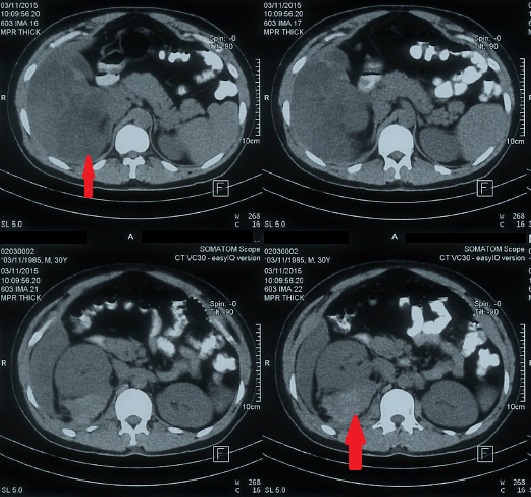

Laboratory investigations revealed a complete haemogram of Hemoglobin (Hb)-3.5gm%; TLC-10,000/cumm, with predominant neutrophilia and platelet count of 20,000/cumm, serum bilirubin-3.9mg%; SGOT/SGPT were 95/90 IU; serum alkaline phosphatase-132 IU; serum proteins-4.9gm%; Prothrombin Time Index (PTI)-1.2; and serum creatinine-1.1mg%. Serology was negative for HIV, HBsAg and anti-HCV. The second ultrasound showed free fluid in the abdomen, bilateral pleural effusion and alteration in the echotexture of liver and kidneys and a hypoechoic lesion of 14cm by 6cm size lateral to right kidney in the right pararenal space extending along right psoas muscle; possibly retroperitoneal haematoma. Follow-up CT abdomen showed possibility of an intra-parenchymal haematoma in the liver with extension to right peritoneum and right psoas muscle haematoma. Active extravasation of contrast on CT scan suggestive of active bleeding was not found [Table/Fig-1]. Surgeon opined for conservative management. Patient was given prophylactic antibiotics, multiple blood transfusions including platelet transfusions and other supportive care. His symptoms and platelet count slowly improved to normal in a week. He was discharged in stable condition with advice to follow-up especially for sonography of the intra-abdominal collection. His thrombophilia profile done after 6 weeks of discharge from the hospital was reported normal.

CT scan abdomen showing intra-parenchymal haematoma in the liver with extension to right peritoneum and right psoas muscle haematoma.